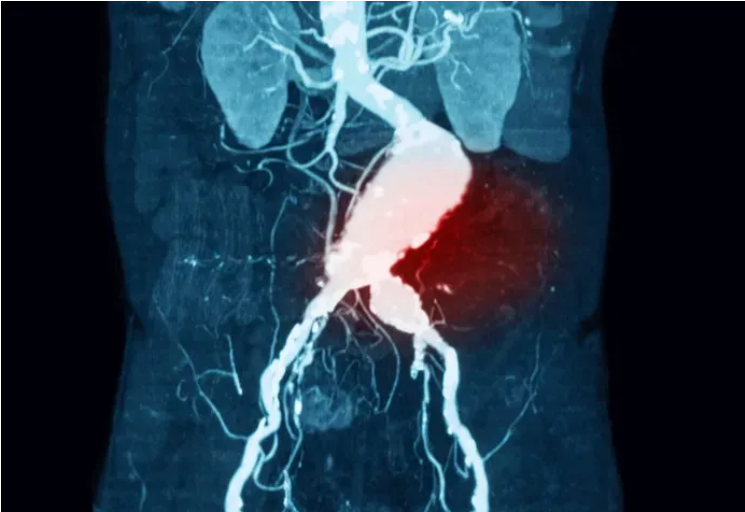

腹主動脈瘤破裂腹主動脈瘤(AAA)是身體最大的動脈——主動脈在腹部部分的擴張。隨著時間的推移,動脈瘤生長緩慢,小動脈瘤通常沒有任何癥狀。然而,較大的動脈瘤和迅速擴大的動脈瘤會引起癥狀,甚至破裂或夾層。AAA破裂和夾層是危及生命的情況,可引起嚴重的低血壓、頭暈、心率加快和突然的劇烈腹痛,如果不能識別和適當治療,將導致嚴重的發(fā)病率和死亡率,未經治療的死亡率接近100%。中間綠色部分為腹主動脈雖然許多AAA患者(腹主動脈直徑大于3cm)被確定為接受了搶先修復術,從而降低了死亡率,但多達50%的主動脈瘤患者的主要表現(xiàn)是動脈瘤破裂。破裂主動脈瘤患者的死亡率難以計算,但據(jù)國內外文獻報道,歷史上的急性死亡率高達90%,而采用當前外科手術方式的急性死亡率高達75%。AAA好發(fā)于65~85歲男性。這些動脈瘤在破裂前通常無癥狀,破裂是一種災難性的并發(fā)癥。導致動脈瘤擴張的原因有直接創(chuàng)傷、慢性感染、急性感染、炎癥等。動脈粥樣硬化性主動脈壁損傷被認為是AAA發(fā)生的主要危險因素,這種傳統(tǒng)觀點最近受到了挑戰(zhàn)。67歲男性,已知腹主動脈瘤,有腰背部和右側腹股溝疼痛3個月的病史。患者行腰椎及骨盆MRI檢查。MRI后立即獲得的連續(xù)軸位CT血管成像(CTA)顯示右側腹膜后大量血腫,并伴有造影劑從主動脈后外側外滲(箭頭)。手術中,看到右側腹膜后大量血腫,病理評估顯示主動脈壁不連續(xù)區(qū)域和相關的機化性血腫。當主動脈壁的機械應力超過壁組織的抗拉強度時,AAA破裂。雖然最初認為簡化的拉普拉斯定律(LawofLaplace)可以預測壁面應力,但實驗證據(jù)表明,壁應力的預測更加復雜,因為它受到動脈瘤位置、結構和腔內血栓的影響。TIPS:拉普拉斯定律是物理學和數(shù)學中的基本原理,它描述了充滿液體的容器內的壓力和容器壁的張力之間的關系。當考慮到動脈中形成的壓力時,它特別相關。簡單地說,拉普拉斯定律就是血管內的壓力與管壁的張力成正比,與血管的半徑成反比。在數(shù)學上,可以表示為:P=2T/r;其中P為壓力,T為張力,r為容器半徑。不同角度的VonMises壁應力輪廓圖,在收縮壓峰值時患者特定的腹主動脈瘤幾何形狀。中間的圖是截面圖。動脈瘤后壁存在高應力區(qū),而近端瘤頸處為壁應力峰值。腹主動脈瘤的大小和擴張速度是預測破裂的最重要因素AAA的大小和擴張速度是預測破裂的最重要因素。根據(jù)一般共識,較大動脈瘤患者應接受手術治療。較小動脈瘤的臨床治療方法存在爭議。對于4.0~5.5cm小動脈瘤的處理,目前臨床研究較少。結論表明,早期介入治療與動脈瘤直徑≥5.5cm時介入治療患者的生存率相似。米國退伍軍人管理局的一項研究表明,早期干預可降低手術并發(fā)癥。在快速擴張的動脈瘤中可以觀察到與初始大小無關的主動脈壁裂隙和破裂。多項研究也顯示,動脈瘤破裂家族史可使腹動脈瘤破裂的風險增加數(shù)倍。另外,與無破裂家族史的患者相比,有破裂家族史的患者發(fā)生動脈瘤破裂的年齡較早(65歲vs.75歲)。大多數(shù)AAA患者的動脈瘤直徑小于5.5cm。由于5.5~5.9cm動脈瘤的1年破裂發(fā)生率顯著增加至9.4%,因此這是手術修復風險低于破裂風險的通常閾值。此外,增加超過0.5cm的動脈瘤破裂風險增加,應及時修復。根據(jù)英國和米國的流行病學資料,大約4%~5%的猝死病例繼發(fā)于AAA破裂。只有約50%的AAA破裂患者到達醫(yī)院,破裂情況下的手術死亡率約為50%;然而,很難知道準確的數(shù)字。動脈瘤的易感因素已確定若干易感因素可增加動脈瘤形成的可能性。這些因素包括年齡較大、男性、收縮期和舒張期高血壓、當前或既往吸煙史以及一級親屬有AAA病史。男性50歲后和女性60歲后,接下來的每一個十年,動脈瘤的風險增加。男性患動脈瘤的可能性是女性的4倍,有一級親屬患AAA的風險增加4倍。吸煙是最重要的可糾正的危險因素,既影響患動脈瘤的可能性,也影響生長加速的速度。病史與體檢雖然理想情況下,患者應該在出現(xiàn)動脈瘤破裂等并發(fā)癥之前就被識別和治療,但超過一半的AAA破裂患者之前有未診斷的動脈瘤,多達30%的AAA破裂患者最初被誤診。據(jù)報道,25%~50%的AAA破裂患者表現(xiàn)為低血壓、腰背痛和搏動性腫塊的典型三聯(lián)征。破裂的可能表現(xiàn)包括原因不明的低血壓、腹股溝疼痛,有時下肢疼痛。其他可能的并發(fā)癥是血尿或消化道出血。因此,對于表現(xiàn)多樣的該病,醫(yī)師應高度懷疑該疾病,并降低評估閾值。在臨床表現(xiàn)上,休克程度因部位、大小和延遲表現(xiàn)而異。前外側壁的破裂直接與腹腔相連,所以通常導致當場死亡有關。后外側壁破裂與腹膜后間隙相通,因此病人通常存活。小破裂較大破裂失血量少,小破裂可初步封閉破裂于腹膜后,減少失血量。據(jù)報道,體格檢查發(fā)現(xiàn)搏動性腫塊的敏感性為51%~100%。研究表明,動脈瘤檢出的總靈敏度隨著動脈瘤大小的增加而增加,對3.0~3.9cm動脈瘤的靈敏度為29%,對4.0~4.9cm動脈瘤的靈敏度為50%,對>5.0cm動脈瘤的靈敏度為76%。肥胖已被證明會降低檢測的準確性。Grey-Turner征,即血液沿腹膜后剝離而累及脅部的瘀斑罕見,但在某些病例中可檢測到外側壁的堅實性。診斷與治療對于血流動力學不穩(wěn)定的患者,可僅根據(jù)癥狀(低血壓、腰背痛和腹部搏動性包塊)或通過床旁超聲確診后將患者送入手術室。對文獻的系統(tǒng)綜述顯示,超聲診斷的靈敏度為98%~100%,特異度為94%~100%。這些結果與在放射科病房進行的超聲篩查相似,后者報告的靈敏度為94%~100%,特異度為98%~100%。腹主動脈瘤(直徑7cm),超聲影像顯示動脈瘤真腔(左下方)與附壁血栓(右上方)主動脈夾層的超聲檢查。在血流動力學穩(wěn)定的患者中,鑒別AAA破裂的首選診斷研究是CT動脈成像(CTA),因為它提供了識別鄰近/受累腎動脈以及動脈瘤形態(tài)的能力。計算機斷層掃描血管造影(CTA)掃描的容積再現(xiàn),一些患者有疊加的動脈瘤節(jié)段。(a,b)患者在t1(左)和t2(右)出現(xiàn)不良演變的圖像。(c,d)患者在t1(左)和t2(右)時的圖像。對于到急診科就診的疑似AAA破裂患者,評估和處置的及時性至關重要,在疑似AAA破裂的病例中,早期與血管外科醫(yī)生會診,同時進行診斷性檢查,有助于促進最終處置到手術室。研究提示,術前液體復蘇策略(包括收縮壓為80~100mmHg的允許性低血壓)可能改善結局。然而,文獻中并沒有隨機對照試驗來證實這些發(fā)現(xiàn)。AAA破裂患者經常需要血液復蘇,往往需要大量輸血。研究表明,自體輸血的患者和較高濃度新鮮冷凍血漿[FFP]輸注的患者(壓積紅細胞[PRBC]:FFP=1:1)有改善的結局。如果不及時治療,AAA破裂在數(shù)小時至一周內幾乎都是致命的。實施開放修復術和血管內修復術的決策復雜,必須考慮患者因素,如年齡、患者合并癥和患者血流動力學狀態(tài)。動脈瘤因素,如位置、大小和形狀;外科醫(yī)生的經驗;以及可用的資源。雖然非隨機研究已經證明血管內修復術可改善發(fā)病率和死亡率,但當這些研究針對患者的血流動力學狀態(tài)進行控制時,這些益處尚未得到證實。此外,對于開放手術PK(比較)?血管內修復術的隨機對照試驗進行的薈萃分析表明,一種修復方法并不優(yōu)于另一種方法。腹主動脈瘤開放修復術腹主動脈瘤腔內修復術腹主動脈瘤腔內修復術前后的CTA影像